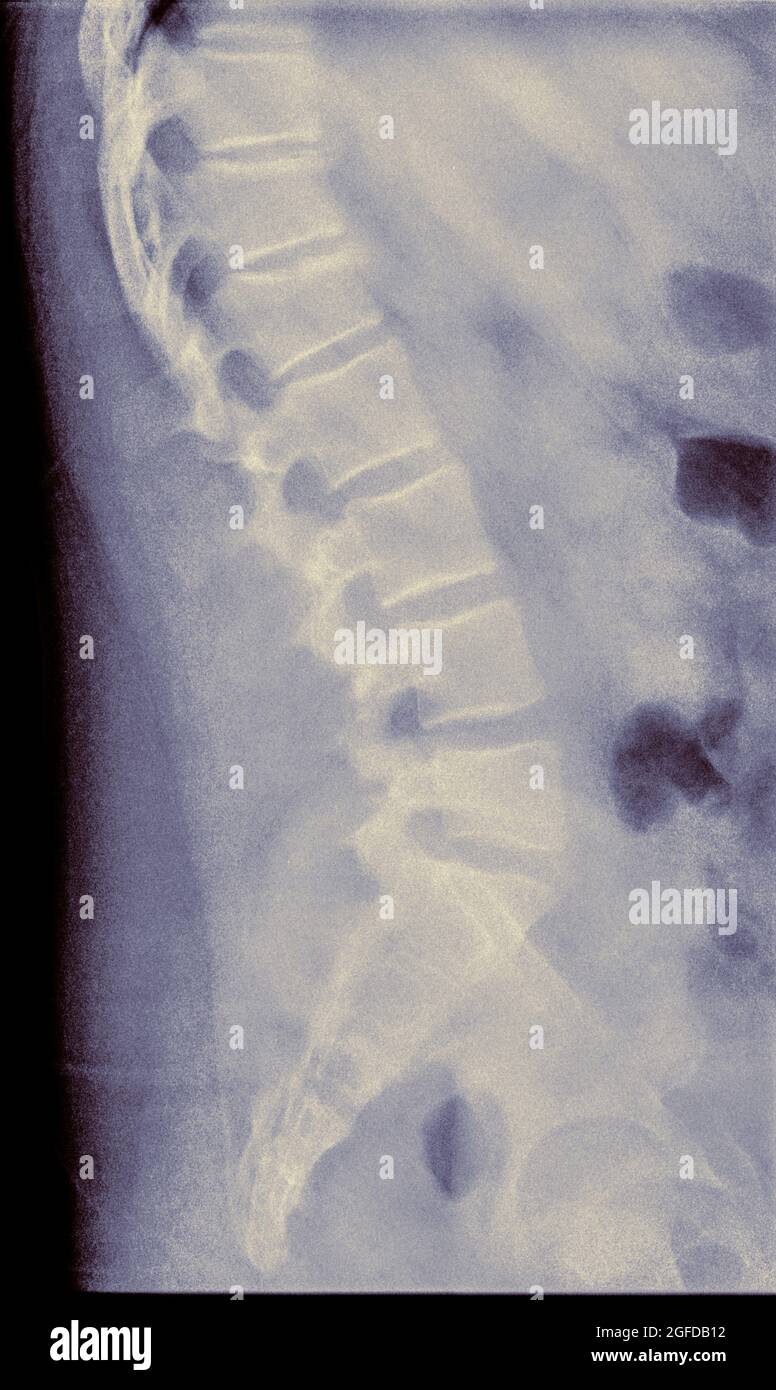

From www.alamy.com

T12 compression fracture hires stock photography and images Alamy A Compression Fracture Of The Lumbar Vertebrae Most Often Occurs As A Result Of  Vertebra fractures are usually due to conditions such as: Vertebral compression fractures (vcfs) of the spinal column occur secondary to an axial/compressive (and to a lesser extent, flexion) load with. A compression fracture is a type of broken bone that can cause your vertebrae to collapse, making them shorter. This often happens to the front of the vertebrae but not. A Compression Fracture Of The Lumbar Vertebrae Most Often Occurs As A Result Of.